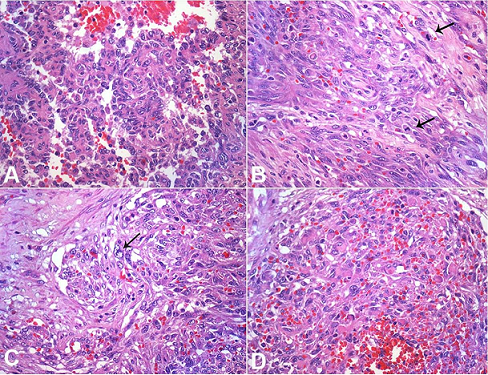

The spleen was enlarged, weighing 1200g (RR: 112g) and measuring 18.0 × 13.0 × 6.5 cm. The splenic capsule had multiple disrupted areas with fibrin deposition. Macroscopic sections showed multiple ill-defined nodular areas; the larger ones were white and firm and smaller ones were blue-red and spongy ( Figure 2). On microscopy, the spleen parenchyma was replaced by anastomosing, irregularly ectatic vascular channels lined by plump mildly atypical lining cells. Intercalated solid fusiform areas consisted of spindle cell fascicles showing moderate nuclear atypia, with frequent mitotic figures. These closely packed vascular channels were filled with red blood cells. Small eosinophilic globules identified in the cytoplasm of the spindle cells were highlighted by periodic-acid Schiff (PAS) reagent ( Figures 3 and 4).

Pathologic findings include splenomegaly with a mean splenic weight of 1073g (RR: 112g). 12 The tumor descriptions range from firm and well-circumscribed to poorly-limited spongy tumor, with hemorrhagic, necrotic, or nodular lesions, and cystic spaces. Scattered tumor areas within the spleen can be seen but eventually the neoplastic process replaces the entire splenic parenchyma. 6,12 Our patient is an elderly woman with clinical and radiological features consistent with the reported characteristics of PSA, and no history of risk factor exposure was identified. Most often PSA is both nodular with relatively homogeneous features associated with poorly circumscribed infiltrative tumor. A vasoformative component consistent with disorganized anastomosing vascular channels lined by atypical endothelial cells with bizarre giant cells are often seen. These giant cells were not found in our case. In addition, intracytoplasmic hyaline globules can be identified with H&E staining; the globules are highlighted with the PAS reaction. Eosinophilic nuclear bodies in the atypical cells are sometimes present. Vascular spaces may present as “slit-like,” “honeycomb-like,” or capillary-like patterns. A solid sarcomatous pattern interfaces with the vasoformative regions. Sheets of malignant epithelioid cells with round to irregular nuclei with vesicular nuclear chromatin may be present. The histological appearance and grade do not directly correlate with the outcome, although the mitotic index and the tumor size are considered prognostic factors. 18 Hemophagocytosis, hemosiderin, extramedullary hematopoiesis, amyloid, and calcification may be found in variable degrees within the tumoral mass. 12 The immunohistochemical profile is characterized by the presence of endothelial markers such as CD31, CD34, FVIII-RA, VEGFR3, and FLI 1. At least two of these markers are required for the diagnosis. Although the presence of histiocytic markers has been considered a clue for the diagnosis of PSA in some reports, they are not ubiquitous. Neuhauser et al. 12 reported that 89% of cases (24/27) exhibited positivity to one or both histiocytic markers (56% were positive for CD68, and 56% for lysozyme). Therefore, “the lack of histiocytic markers may not dissuade from diagnosis of angiosarcoma, if atypia and increased mitotic activity, shared with angiosarcomas, are present” (Dr. Neuhauser personal communication). The histomorphological features of the index case are those of PSA, confirmed by the immunohistochemical markers of vascular origin. The presence of atypia and the high Ki67 index, plus the absence of histiocytic markers in tumor cells helped rule out the diagnosis of littoral cell angioma, which is the main differential. In the series of Falk et al. 7; only 1 case in 23 presented positivity for CD68. These markers are not found in angiosarcoma of sites other than the spleen. The mitotic index by Ki 67 usually varies between 5% and 10%. In the case reported by Coppola et al., 15 the positivity for CD 68 was interpreted as possible littoral cell origin of the neoplastic cells. Littoral cell angiomas are splenic vascular tumors that mimic the findings of hypovascular angiosarcomas but generally do not diffusely involve the spleen and do not show atypia. The differential diagnosis of splenomegaly with a complex mass includes hemangiomas, littoral cell angioma, lymphangioma, hemangiopericytoma, lymphoid-origin neoplasia, and metastatic disease. In the setting of metastatic disease, ovarian carcinoma is among the more common primary tumors that metastasizes to the spleen and should be considered in the differential diagnosis although the histologic features are not those of PSA. 23 The presence of concomitant malignant tumors in patients with PSA—markedly breast cancer, lymphoma, colon cancer, skin cancer, and renal cell carcinoma—has been reported. 24